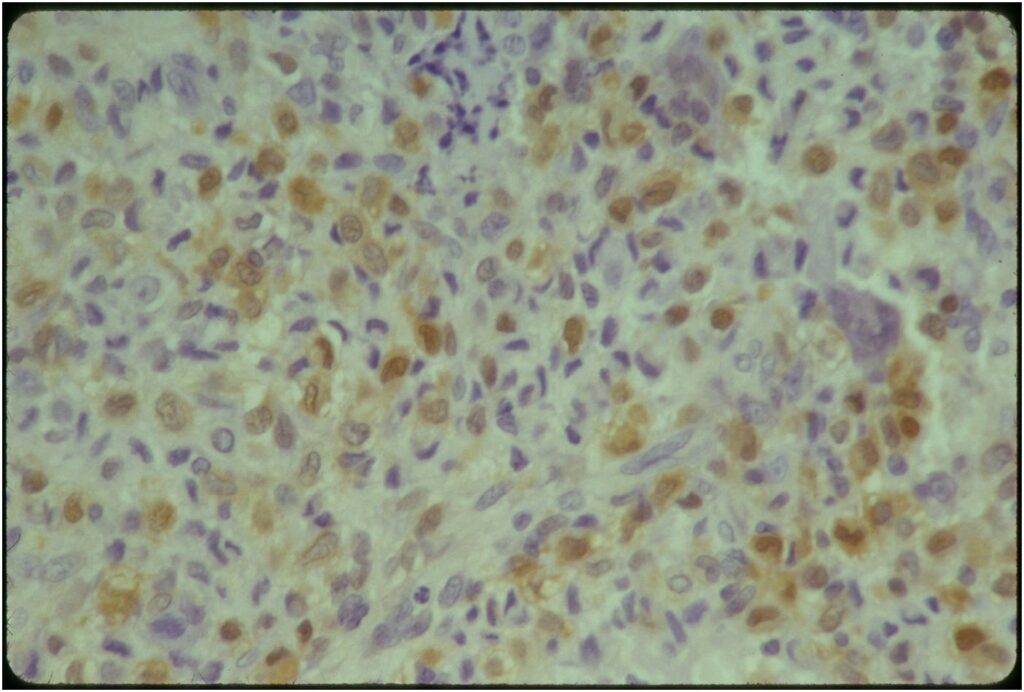

Microscopic Pathology

- Variable appearance depending on percentage of cells, necrosis, cartilage matrix formation and ABC change

- Chondroid matrix in up to 15% of tumor

- ABC component 5-15% of tumors

- The tumor is composed of chondroblasts that have a distinct, thick cell membrane. The thick cell membrane gives it a “Chicken Wire Fence Appearance,” especially when the cell membranes are calcified